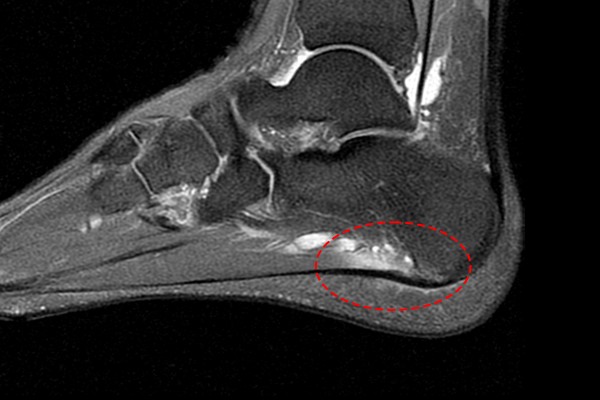

발바닥 부착부에도 염증이 확인되어 족저근막염(Plantar fasciitis)을 진단하였습니다.

96707d45bfa78bc815f4e3f85a28a525_1757924029_8235.jpg

보통 족저근막의 두께가 4~5mm 이상일 때 수술적 치료를 시행하게 되는데, 환자분의 족저근막 두께는 5mm 정도로 측정되었고, 앞서 2년간 여러 보존적 치료를 시행했음에도 증상이 호전되지 않았기 때문에 환자분께 현재 발바닥 상태와 수술적 치료의 필요성을 설명드렸고, 족저근막 내시경 유리술(Endoscopic plantar fascia release)을 시행하였습니다.